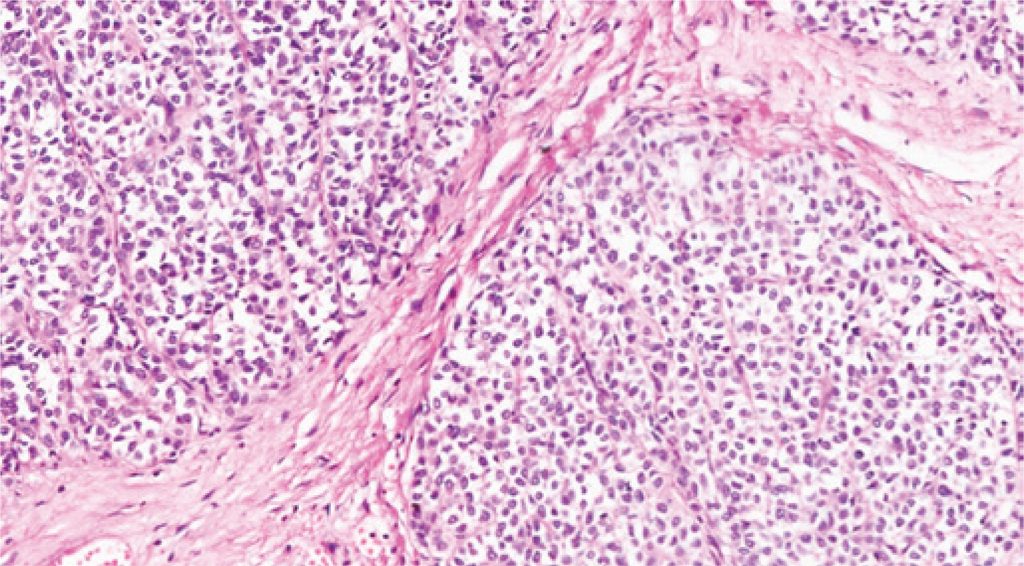

Tumor neuroendócrino primário do fígado: descrição de caso e revisão da literatura

Tumores carcinoides primários do fígado são neoplasias derivadas de células neuroendócrinas produtoras de hormônios, extremamente raras e de difícil diagnóstico antes da biópsia, ressecção cirúrgica ou mesmo da necrópsia. Em recente publicação, descreveram-se apenas 94 casos dessa afecção. É uma doença sem predileção por sexo e que, aparentemente, não tem associação com cirrose, nem com doença hepática preexistente. O tratamento que se demonstra mais eficaz é a hepatectomia, cuja extensão da ressecção é determinada pelo tamanho e pela localização das lesões.